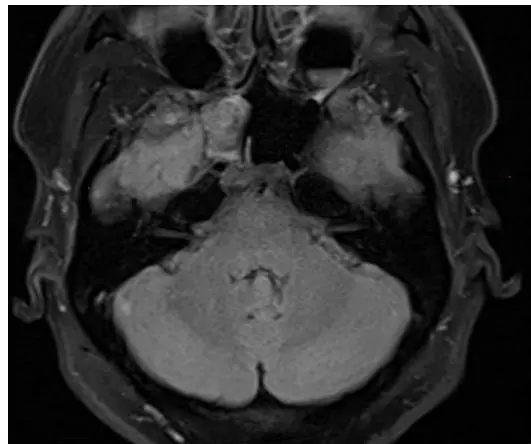

我们从病例报告中提取了MRI图像,并向微调后的模型查询:"影像中观察到了什么?"

来自真实医学病例的测试图像

作为参考,以下是三个来源对同一图像的说法:

ChatGPT (GPT-5.3)

这是后颅窝水平的轴向脑MRI。脑干两侧有两个相当对称的大肿块,位于小脑桥角。病变看起来是脑外的,正在压迫小脑和脑干等附近结构。

我们的微调模型

右侧小脑桥角区域的大肿块。肿块在T1上与灰质等信号,在T2上高信号,钆增强明显。肿块延伸至右侧内耳道,似乎包裹了右侧第八颅神经。

真实标签(来自论文)

冠状位T2加权MRI显示脑室和颞叶的高分辨率可视化,有证据表明脑组织疝出至蝶窦右侧隐窝。

显然,微调后的模型和ChatGPT都错了。

然而,在比较ChatGPT和我们的模型的响应时,值得注意的是:

- ChatGPT识别了"双侧小脑桥角肿块"。它本质上是对一种常见病理(听神经瘤)进行模式匹配,但完全错误。

- 我们的微调模型犯了类似的定位错误,但采用了专业的放射学术语。它利用了结构化信号表征(T1/T2强度、钆增强)和临床术语,与真实标签中使用的类似。